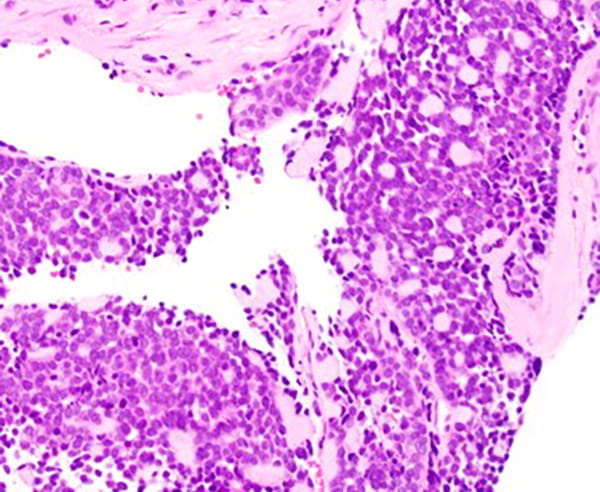

The tumor predominantly grows in the submucosal areas, forming cribriform nests, ductal structures, trabecular arrangements, or solid sheets. The tumor cells are basaloid with scant cytoplasm. Focal areas of squamous differentiation, characterized by eosinophilic cytoplasm, are observed. The overlying squamous mucosa exhibits high-grade dysplasia.